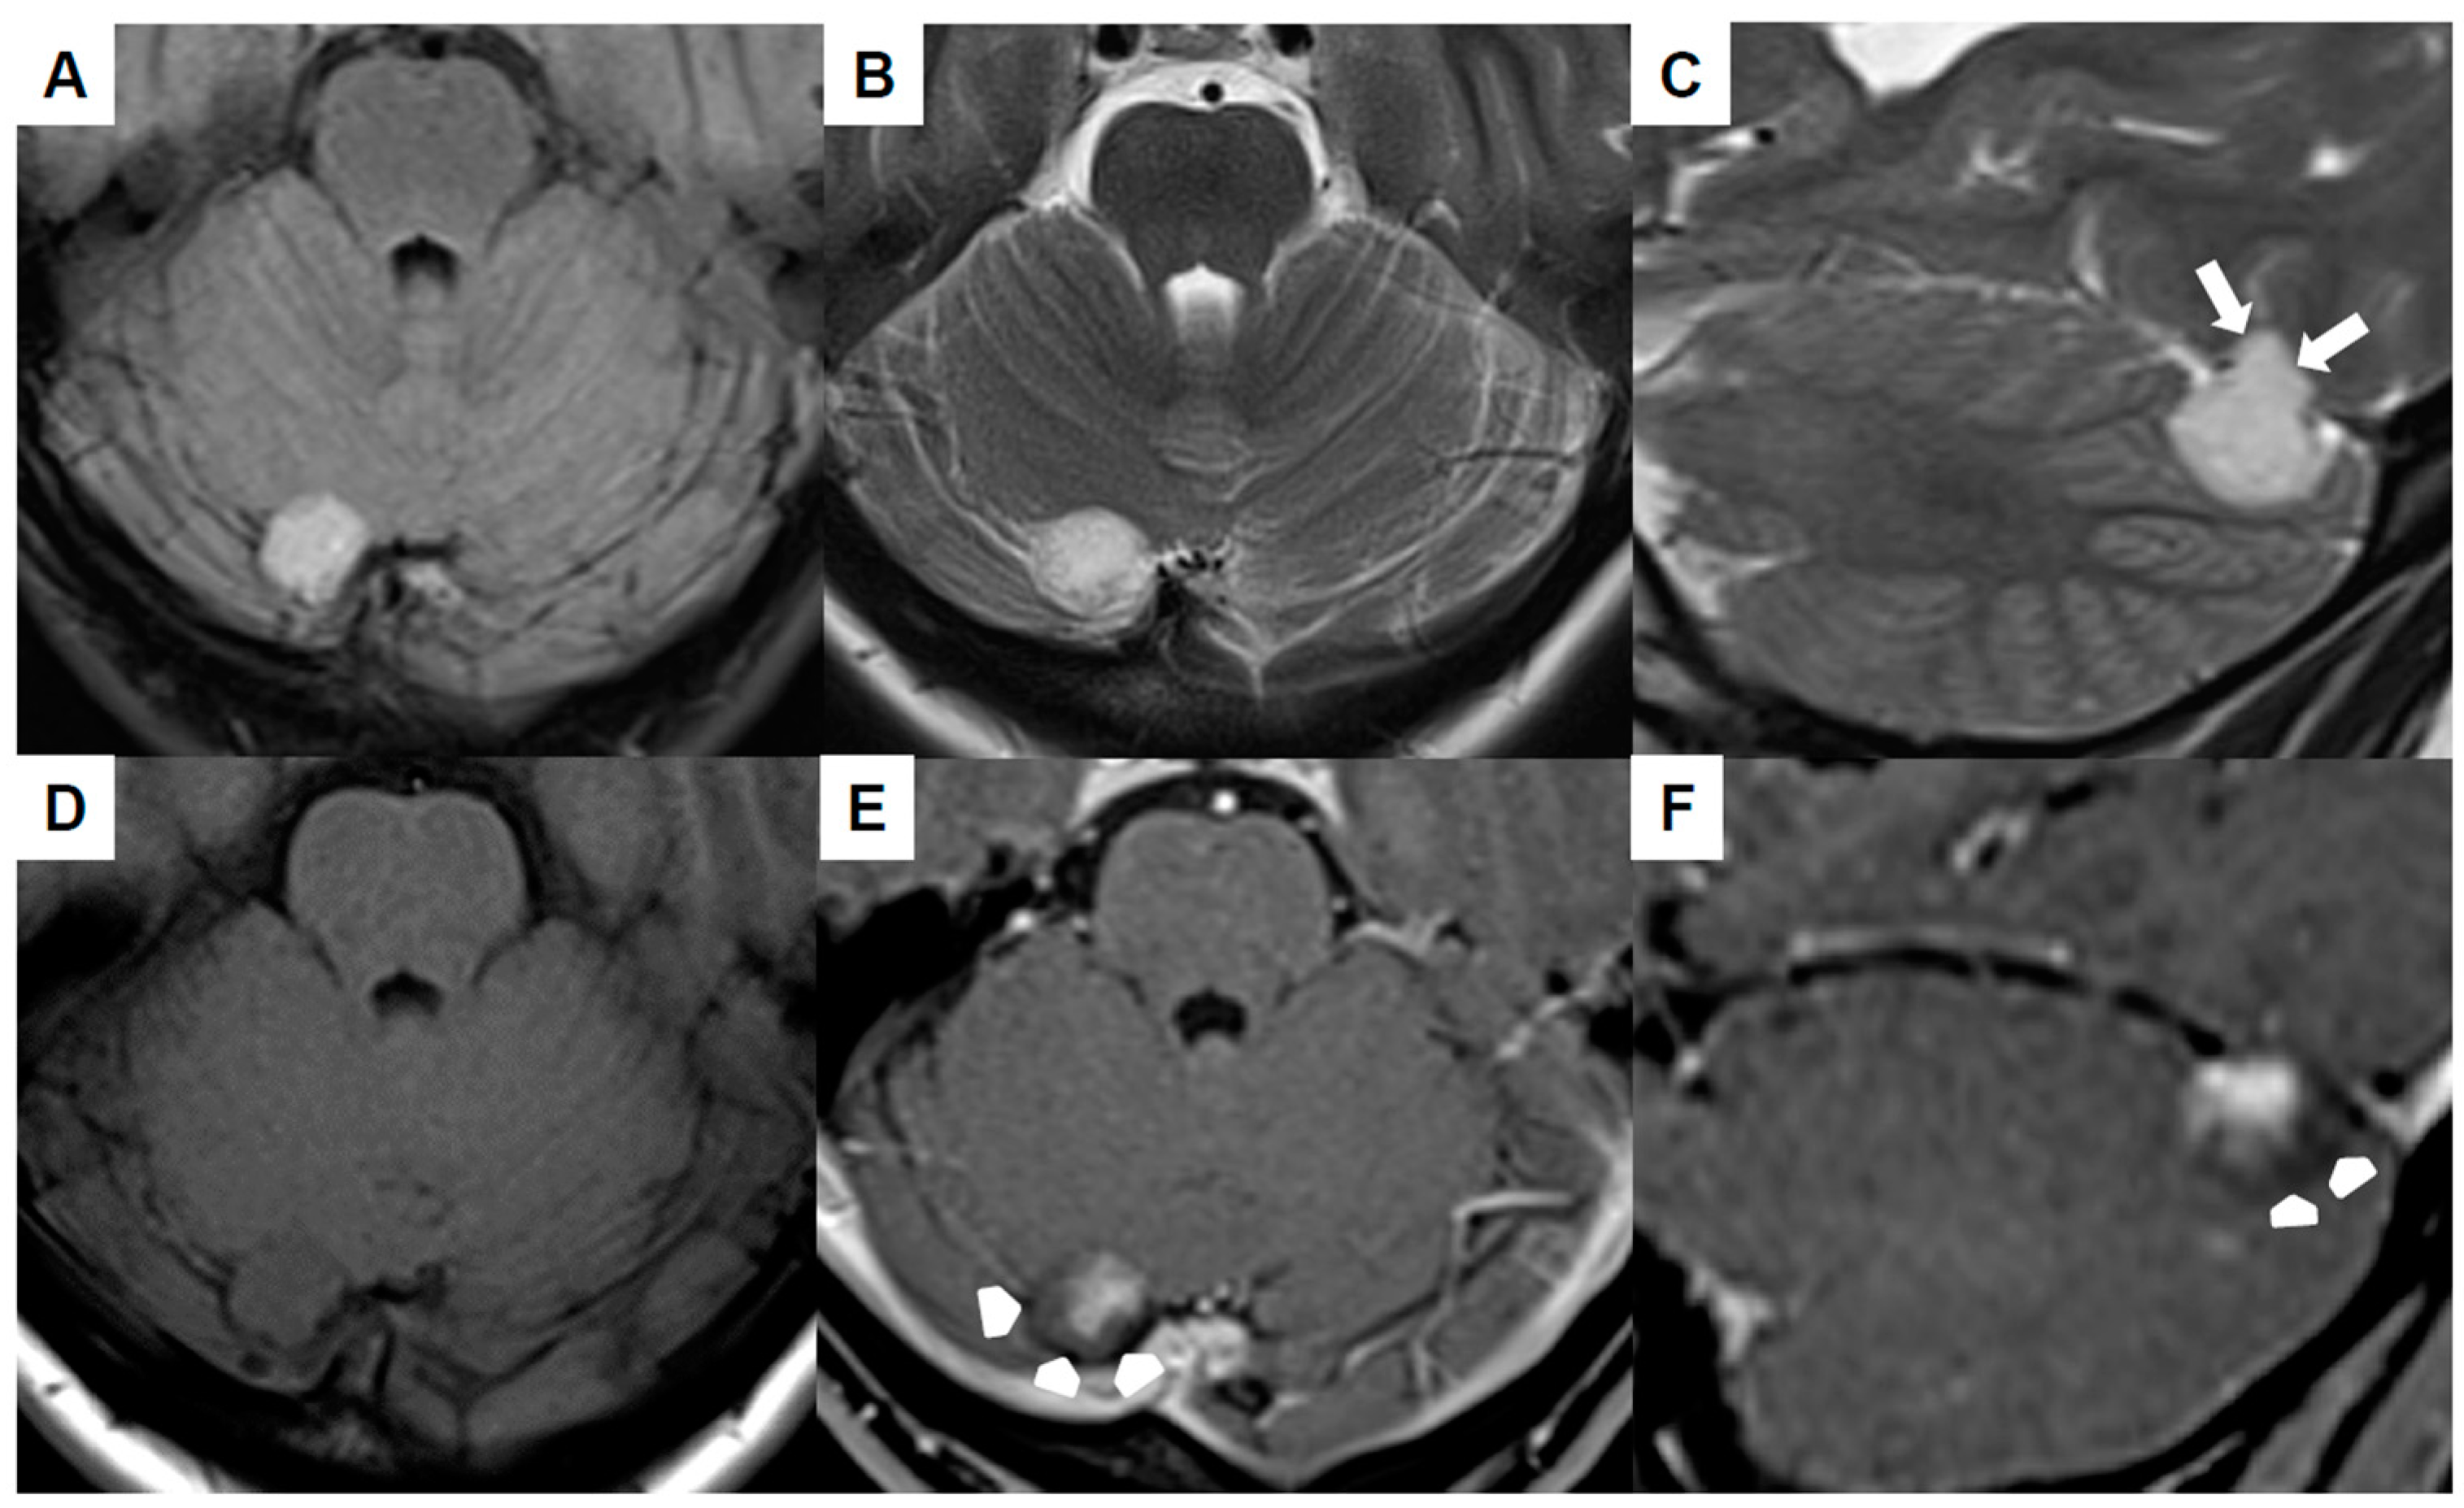

| Our first case | 34 | F | Extra-axial infratentorial on the right | Dizziness, headache, migraine (unrelated to venous hemangioma/no improvement of symptoms postoperatively) | No | 6 years | No recurrence at 3 months, No neurological deficits |